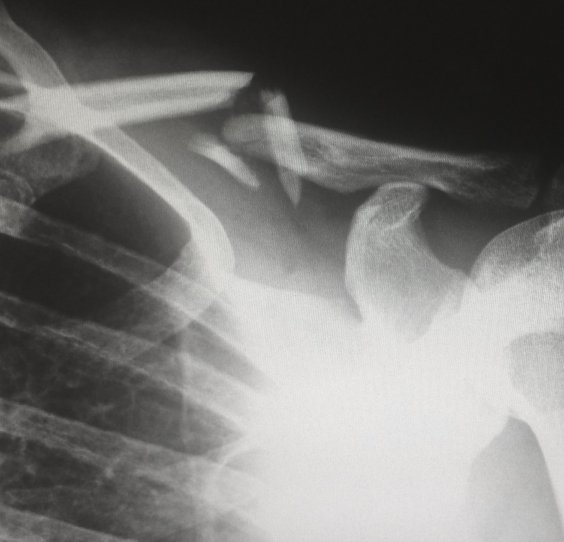

Pomoč pri sanaciji poškodb